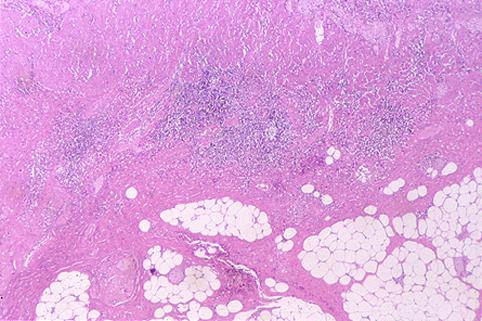

疾患(病理主体)の分類炎症性・潰瘍性疾患/クローン病

部位(臓器別)小腸/回腸

検査方法ミクロ